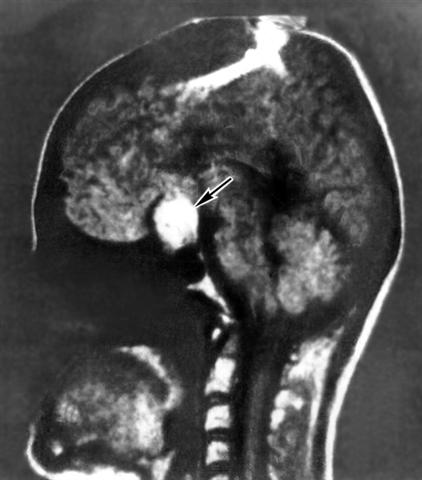

Рис. 3. Томограмма головы, полученная методом ЯМР-томографии (сагиттальный разрез), больной с пролактиномой (указана стрелкой).